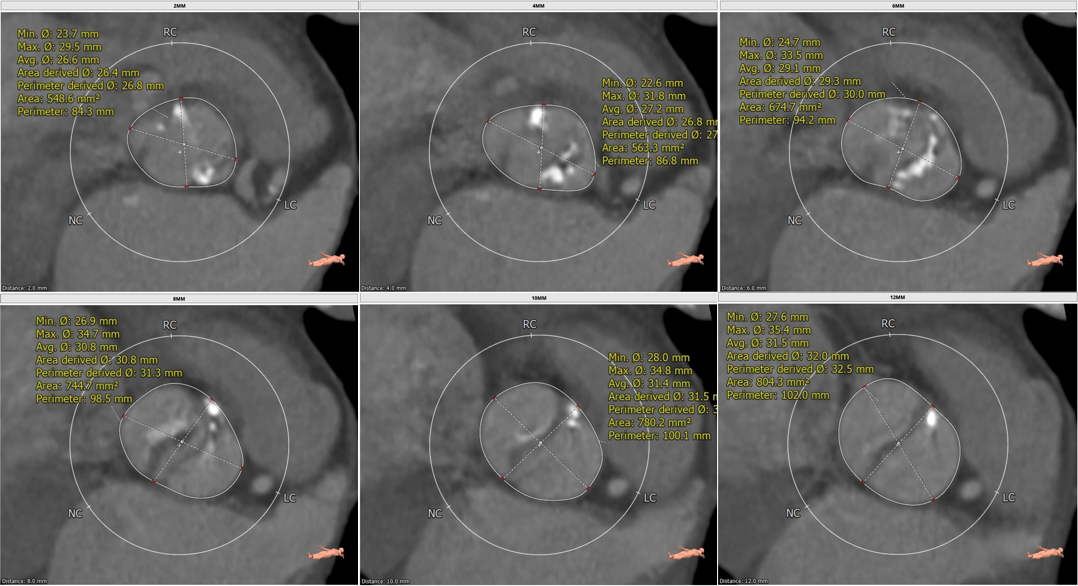

CT分析结果

该名患者为Type 0型二叶瓣,钙化分布不对称,瓣叶有轻度增厚。瓣环最短径为19.6mm,最长径为25.2mm,平均瓣环直径为22.4mm。左冠开口高度15.6mm,右冠开口高度15.9mm。

瓣环

左室流出道

主动脉窦

窦管交界处

升主动脉

瓣上多平面分析结果